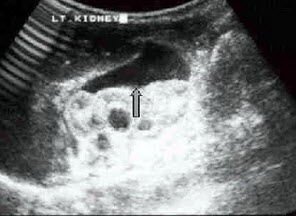

6、单项选择题

某患者左肾超声声像图如下,最可能的诊断为()

A.多发性肾囊肿

B.肾结核

C.多囊肾

D.重度肾积水

E.中度肾积水